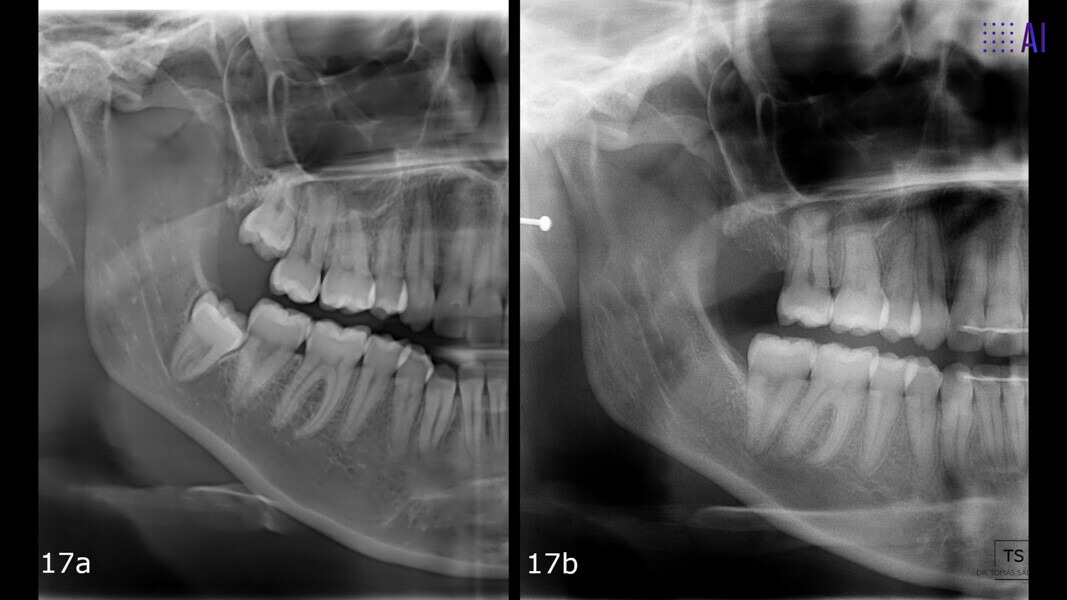

The 23-year-old dolichofacial female patient complained of not being able to chew properly. Facial examination showed a convex profile, an enlarged lower facial height, and a skeletal Class III malocclusion (Figs. 1–3). Intra-oral examination revealed an Angle Class III right subdivision malocclusion, anterior open bite, no overjet and a maxillary dental midline deviated about 3 mm to the right compared with the mandibular dental midline (Fig. 4). The panoramic radiograph confirmed previous extraction of the maxillary right first premolar and the presence of all four third molars (Figs. 5 & 6).

The treatment objectives included closing the anterior open bite, achieving a bilateral Angle Class I relationship and a proper overjet and overbite, correcting the midline discrepancies, and achieving a profile harmonisation. The treatment plan consisted of orthodontic camouflage treatment with asymmetric distalisation in three of the four quadrants using Invisalign aligners (Align Technology) and third molar extraction. The Invisalign Comprehensive package was chosen, and 63 pairs of aligners were used (Figs. 7–10). Each aligner was worn for 20 hours a day for one week each. The use of Class III elastics on both sides was indicated. Afterwards, ten refinement aligners were needed to improve the interdigitation on the right side (Figs. 11 & 12).

The total treatment time was 15 months. An Angle Class I relationship was established along with adequate anterior and canine guidance, establishing a functional occlusion. This not only ensures optimal masticatory function but also protects the teeth and the temporomandibular joint from excessive force. Maxillary and mandibular fixed retention were installed at the end of the treatment (Figs. 13–19).